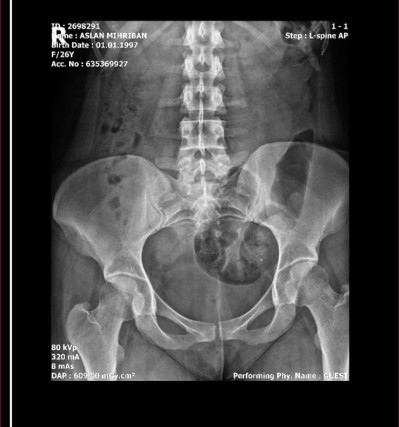

İki bobregimde çok ağrıyor bugünlerde baya artmış hem böbreklerim ağrıyor hemde karnıma atıyor ağrısı bugün üroloji bölümüne gittim röntgen kan idrar falan istedi ama doktor çıkması gerekti bakmadı tahlillere bende öylesine bir e nabiza baktım hele sizde bakın doktor değiliz diyebilirsiniz ama öyle atmak istedim yorumlarınızı bekliyorum;) sol tarafta küçük küçük siyah nokta gibi şeyler var onlar ne acaba merak ettim

Canım yanlış yorum yapmak istemiyorum ama sağ tarafında ağrı var mı belki taş olabilir şu görüntüler rapor diye bi döküman olması lazım o dökümanı indirip atar mısın

Raporlamamışlar vala rapor yok. Her iki tarafta da aşırı ağrı var fotoya göre sol tarafta o küçük küçük şeyler var bende onlardan şüphelendim ama anca doktor görünce anliyacaz

Gaz sıkışması da olabilir